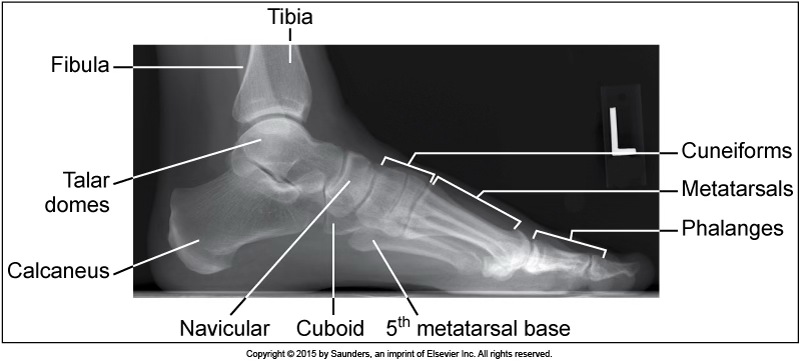

medialateral foot

accurate positioning